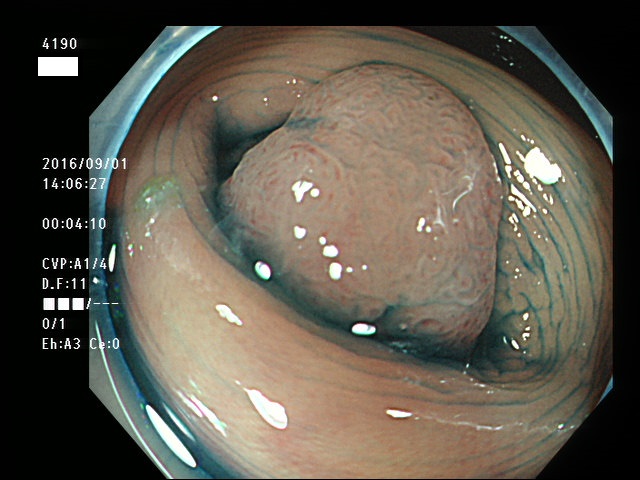

下記の写真は憩室内癌が腹腔全体に広がり、その原発巣(憩室)を内視鏡で確認した世界的に極めて珍しい報告の写真です。(以下、この報告が正しいと仮定して話を進めます)癌が全く、粘膜面に露出していません。上記の写真とは全く、異質の所見です。これは「憩室の壁が薄いから」という解剖学的理由では説明が付かない現象です。憩室内癌は、次に述べる「虫垂粘液腫瘍」に似た、独特な生物学的特性があるように思われます。いずれも慢性的な炎症を母地にしていると思われますので、Colitic Cancer(大腸炎に発症する癌)に近いのかもしれません。今後の分子生物学的解明が待たれます。

憩室内に発生した癌が腹腔内に転移した症例報告

の内視鏡写真